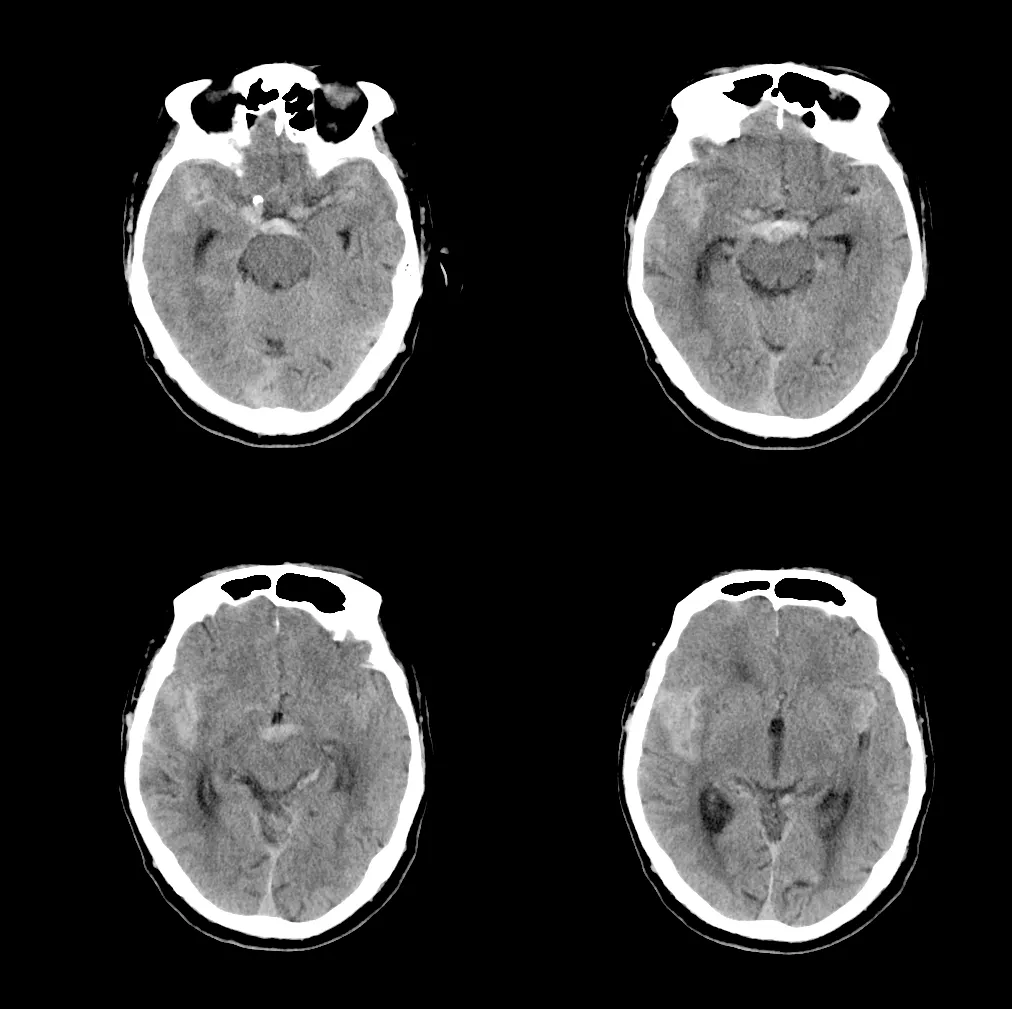

影像表现为双侧额,颞叶,左侧桥臂,左侧基底节区多发病灶,脑基底池

蛛网膜下腔出血,鞍上池,四叠体池,双侧外侧裂池高密度.